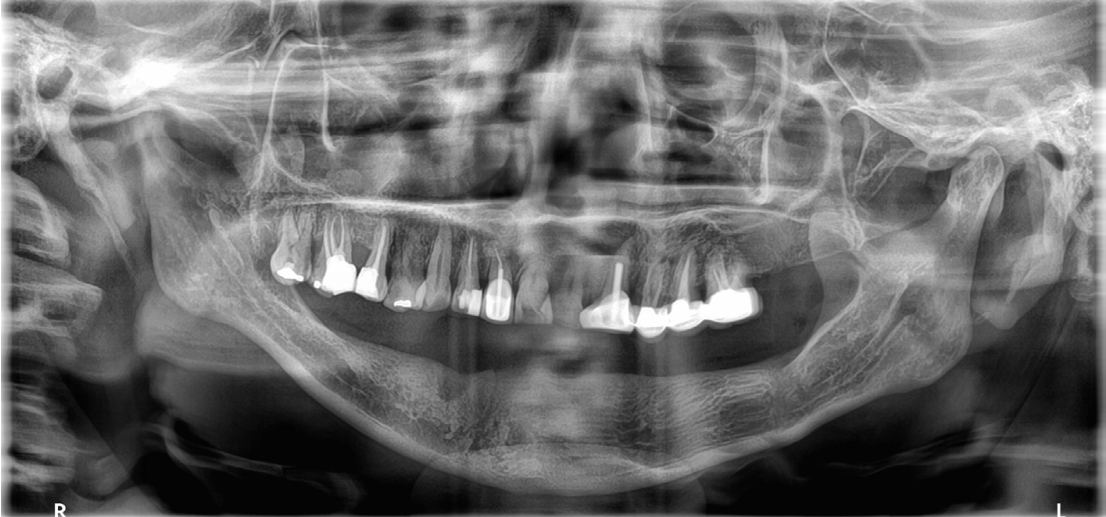

Fig. 3.

The lower jaw is edentulous with severe alveolar bone loss.

jkda-2025-63-7-001f3.jpg